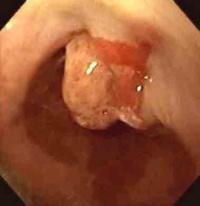

食管黏膜